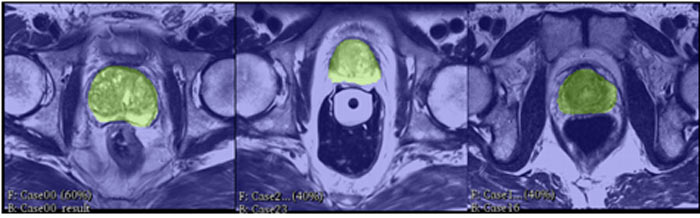

Pak tu máme také volumetrické 3D renderování vnitřku těla pacienta. Tato technika využívá data z CT a magnetické rezonance, které jsou pak dodatečně zpracována, aby zobrazila "komplexní anatomické informace". Doktoři budou moci díky tomu nahlížet na vybrané části těl z různých perspektiv, aby mohli lépe vidět jejich prostorovou strukturu.